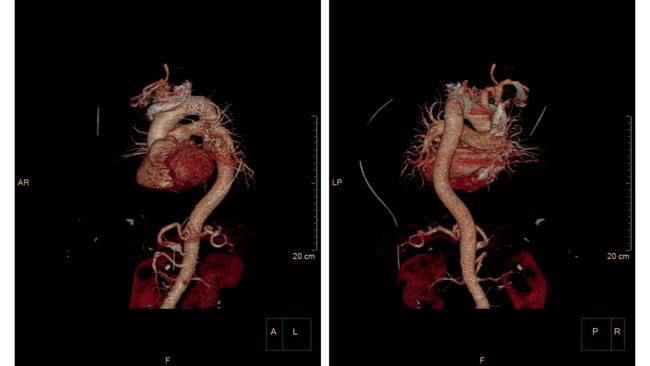

An 83-year-old man with severe aortic stenosis underwent implantation of a 29-mm SAPIEN-3 (Edwards Lifesciences) transcatheter aortic valve (TAV) appropriately sized for an aortic annulus area of 543.6 mm2. Immediately post-implantation, due to loss of capture of the rapid pacing sequence (pacing failure) during deployment (Figure 1A), the TAV lost contact with the aortic annulus and migrated to the ascending aorta (Video 1). After a brief period of rocking motion within the ascending aorta (Figure 1B), the TAV was finally embolized at the distal part of the aortic arch (Figure 1C; Videos 2 and 3). Due to a significant residual aortic valve regurgitation, an additional 29-mm balloon-expandable TAV was successfully advanced through the first TAV and deployed in the native valve (Figure 2A). Having assessed that the embolized TAV was positioned distally to the ostia of the left common carotid and the left subclavian artery with ample patency of possibly jeopardized vessels (Figure 2B), post-dilation with a 29-mm balloon was performed to secure the valve against the aortic wall (Figure 2C).